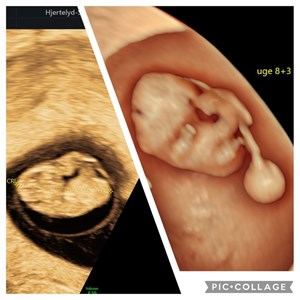

Billeder fra livets begyndelse ✨ Scanning i 9. graviditetsuge. Billede i 2D og 3D. Læg mæ...

Bare 11 dage mellem de 2 billeder ! Fantastisk hvilket potentiale der er i sammensmeltnin...